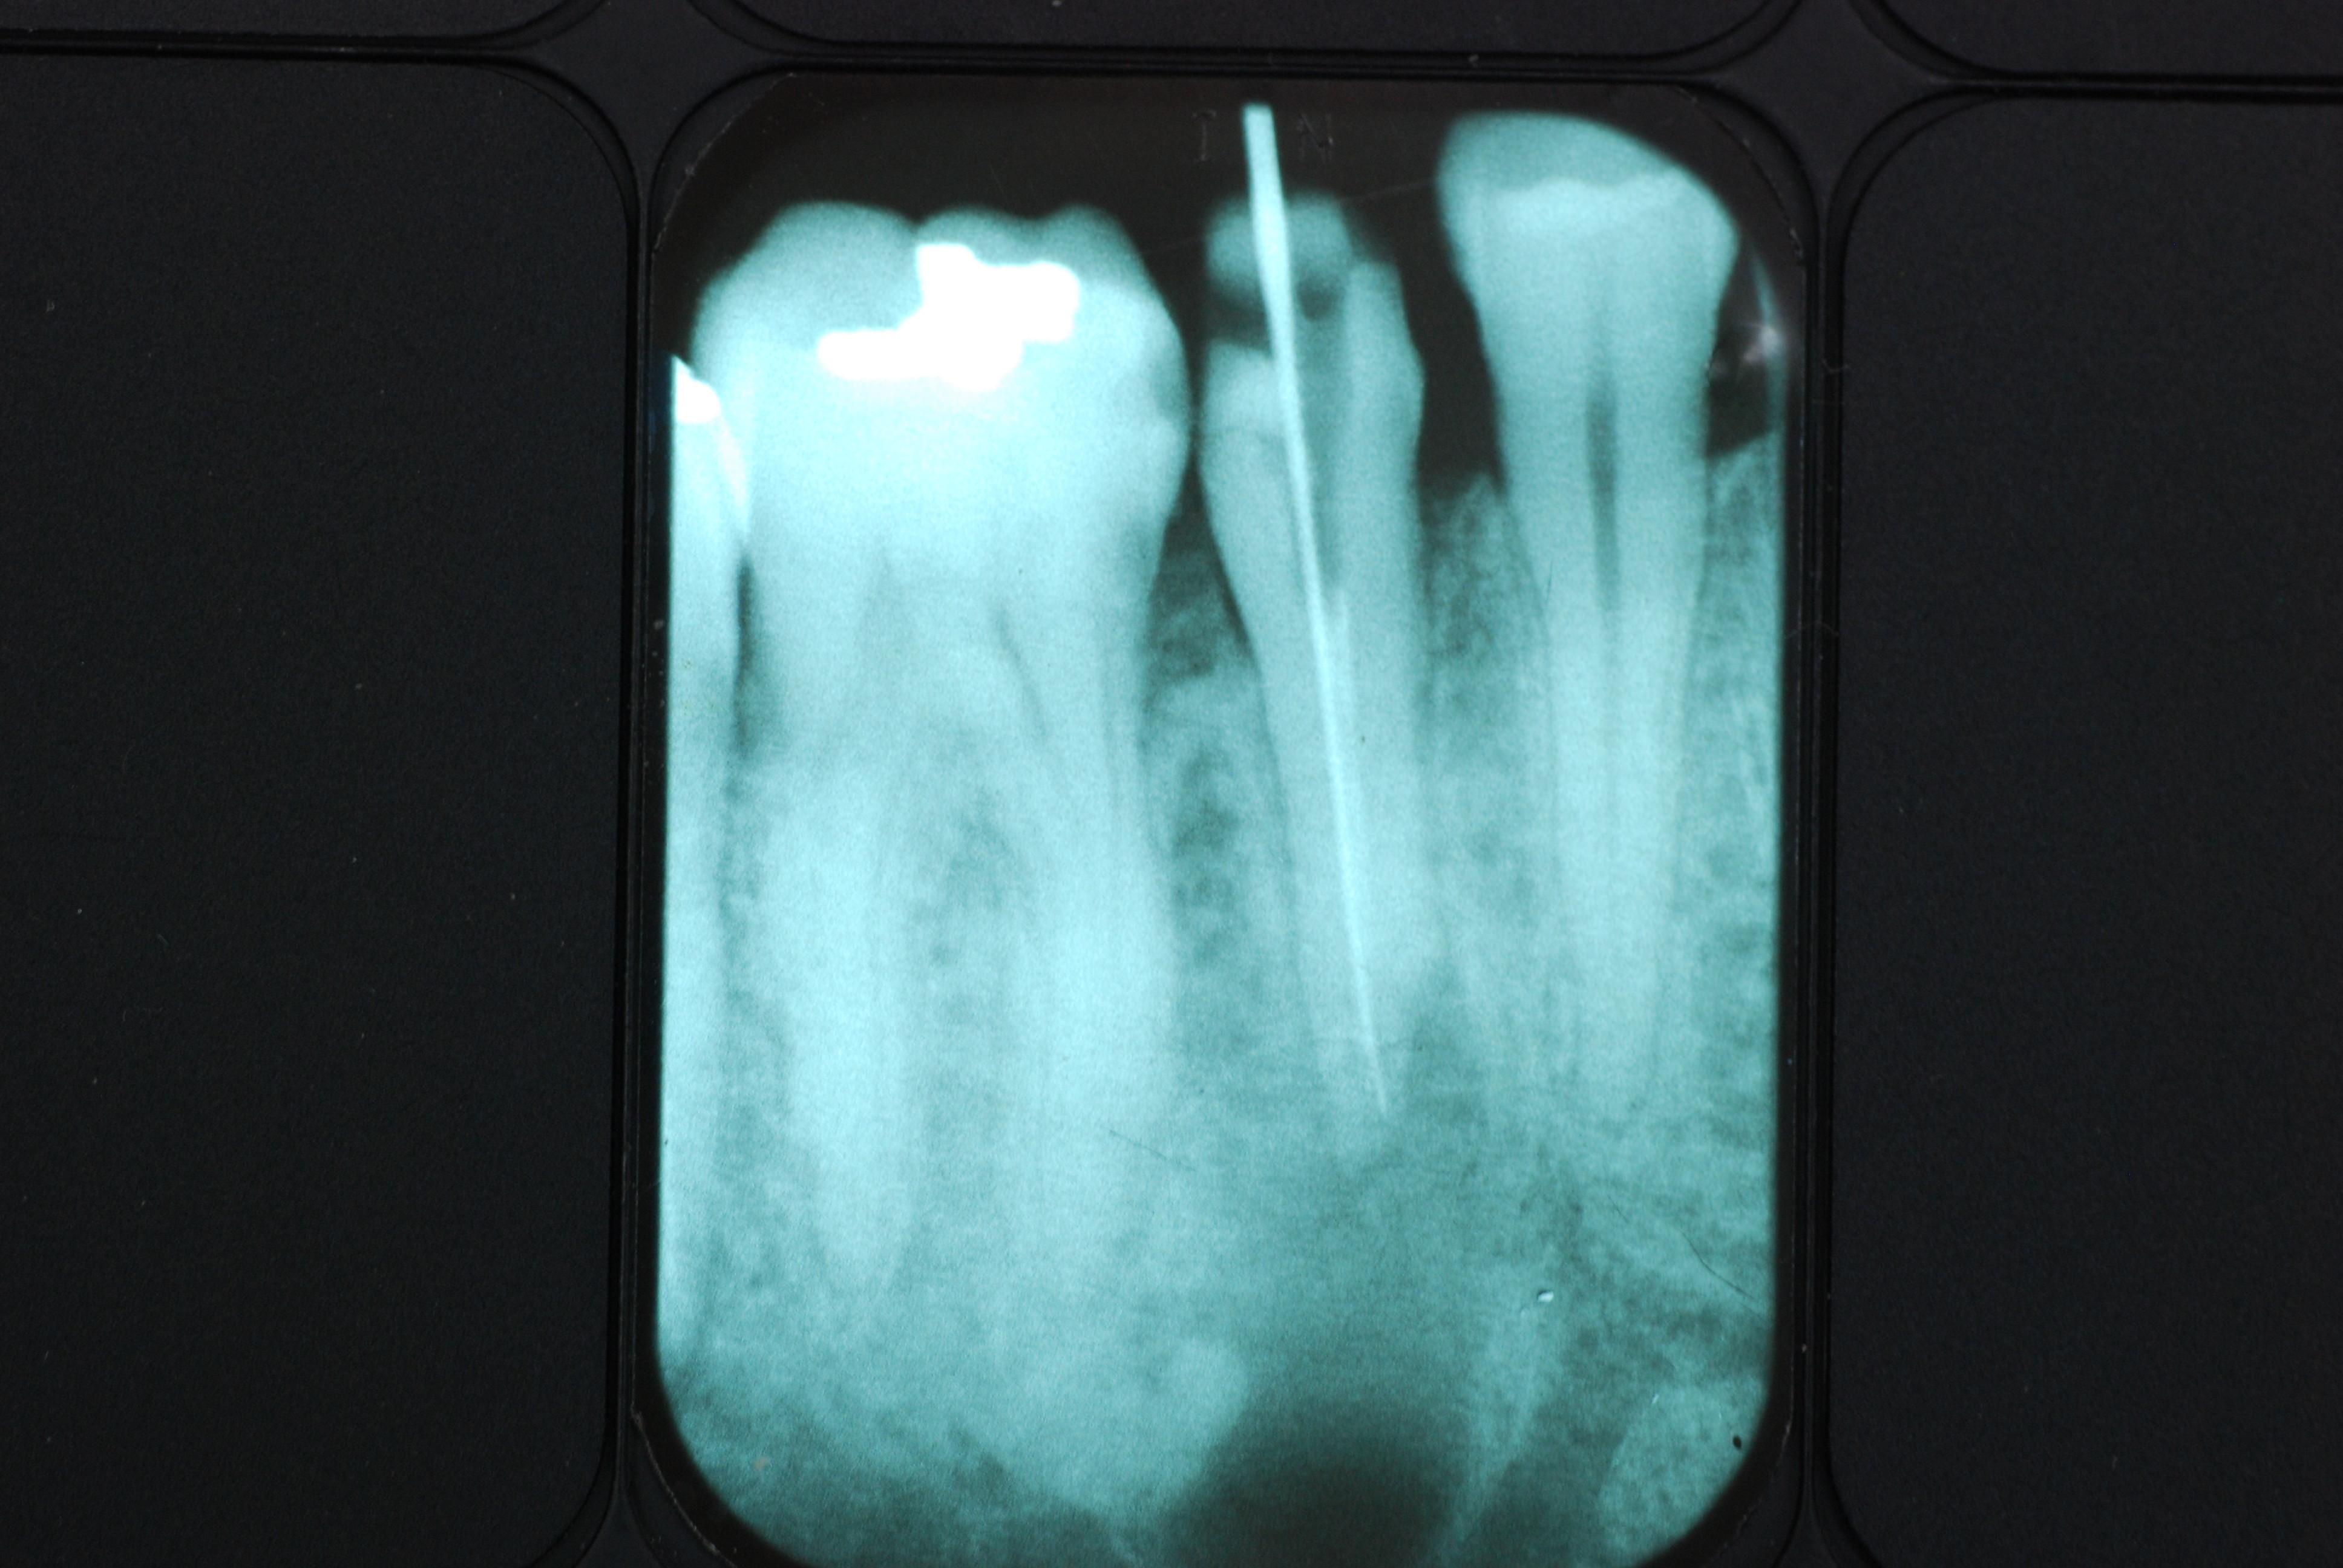

必ずばい菌が侵入しないようにしてばい菌である虫歯を除去します。

銀歯の下はばい菌だらけです。こういうのはよくあります。取り残しですね。![treatment_05[1]](https://livedoor.blogimg.jp/netdental/imgs/3/a/3ad019d0-s.jpg)